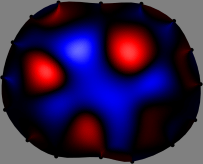

Figs. 3 and 4 compare the performance of the proposed FER method in (20) with the standard regularized least-squares method ((19) when \mathcal{R} is the identity matrix). The regularization parameter of the standard method was heuristically chosen for its best performance, and the parameter of the FER method was set to be one of three different values λ=0.05,0.2,𝜆0.050.2\lambda=0.05,0.2,\infty. The injection current was 1 mARMSRMS{}_{\tiny{\mbox{RMS}}} at 100 kHz, and the frame rate was 9 frames per second. The reference frame at t0subscript𝑡0t_{0} was obtained from the maximum expiration state. The measured data, 𝐕˙(tm)˙𝐕subscript𝑡𝑚\dot{\mathbf{V}}(t_{m}), represent the voltage differences between each time tmsubscript𝑡𝑚t_{m} and t0subscript𝑡0t_{0}. The blue regions, which denote where conductivity decreased by inhaled air, increased during inspiration and decreased during expiration. The FER method with λ=𝜆\lambda=\infty was clearly more robust than the standard method that produced more artifacts originated from the inversion process.

Figure 4: The reconstructed images of the conductivity change of the subject B by the standard regularized least square method and the proposed fidelity-embedded regularization (FER) method for three difference values λ=0.05,0.2,𝜆0.050.2\lambda=0.05,0.2,\infty. Here, the time step is 0.55 seconds (tm+5tm0.55subscript𝑡𝑚5subscript𝑡𝑚0.55t_{m+5}-t_{m}\approx 0.55).